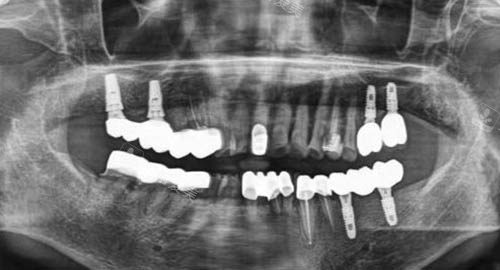

比如较高的口腔CT设备,可以清晰地呈现口腔内部的结构,帮助医生更准判断病情,制定出更科学合理的治疗方案。

种牙和矫正是吉林市德立联合口腔的两大特色项目。

在种牙方面,医院拥有经验充足的种植医生团队,他们熟练掌握各种种植技术,能够根据患者的不同情况选择合适的种植方案。

无论是单颗牙缺失还是多颗牙缺失,都能为患者提供优质的种植服务。

而且,医院使用的种植体质量可靠,术后结果良好,能让患者修复正常的咀嚼功能。